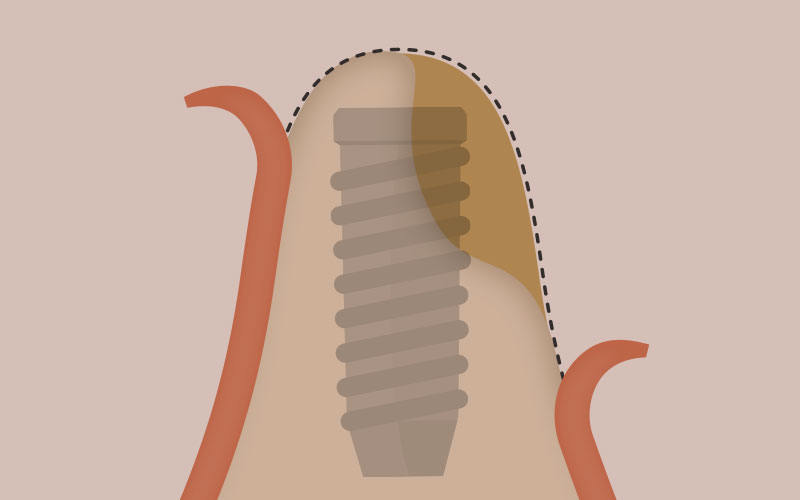

インプラント体は

人工の歯の根

インプラントそのものはチタンで出来ています。歯の根と同じように約10mm程度の長さをしているチタン製の人工物が、歯の根の代わりにあごの骨に埋め込まれます。

WHATS.02

インプラント体は

骨と結合して安定

インプラント体の素材であるチタンには、時間の経過とともに骨と一体化して固まってしまう性質があり、この作用を利用して、人工の歯の根をしっかりと固定させています。インプラントはネジの様な形状で溝が刻まれており、スクリューさせてあごの骨にしっかりと埋め込めるようになっています。またインプラントのメーカーごとに、より良く骨と結合させるために工夫が凝らされた表面形状で作製されており、これがメーカーごとの大きな性能の違いとなっています。